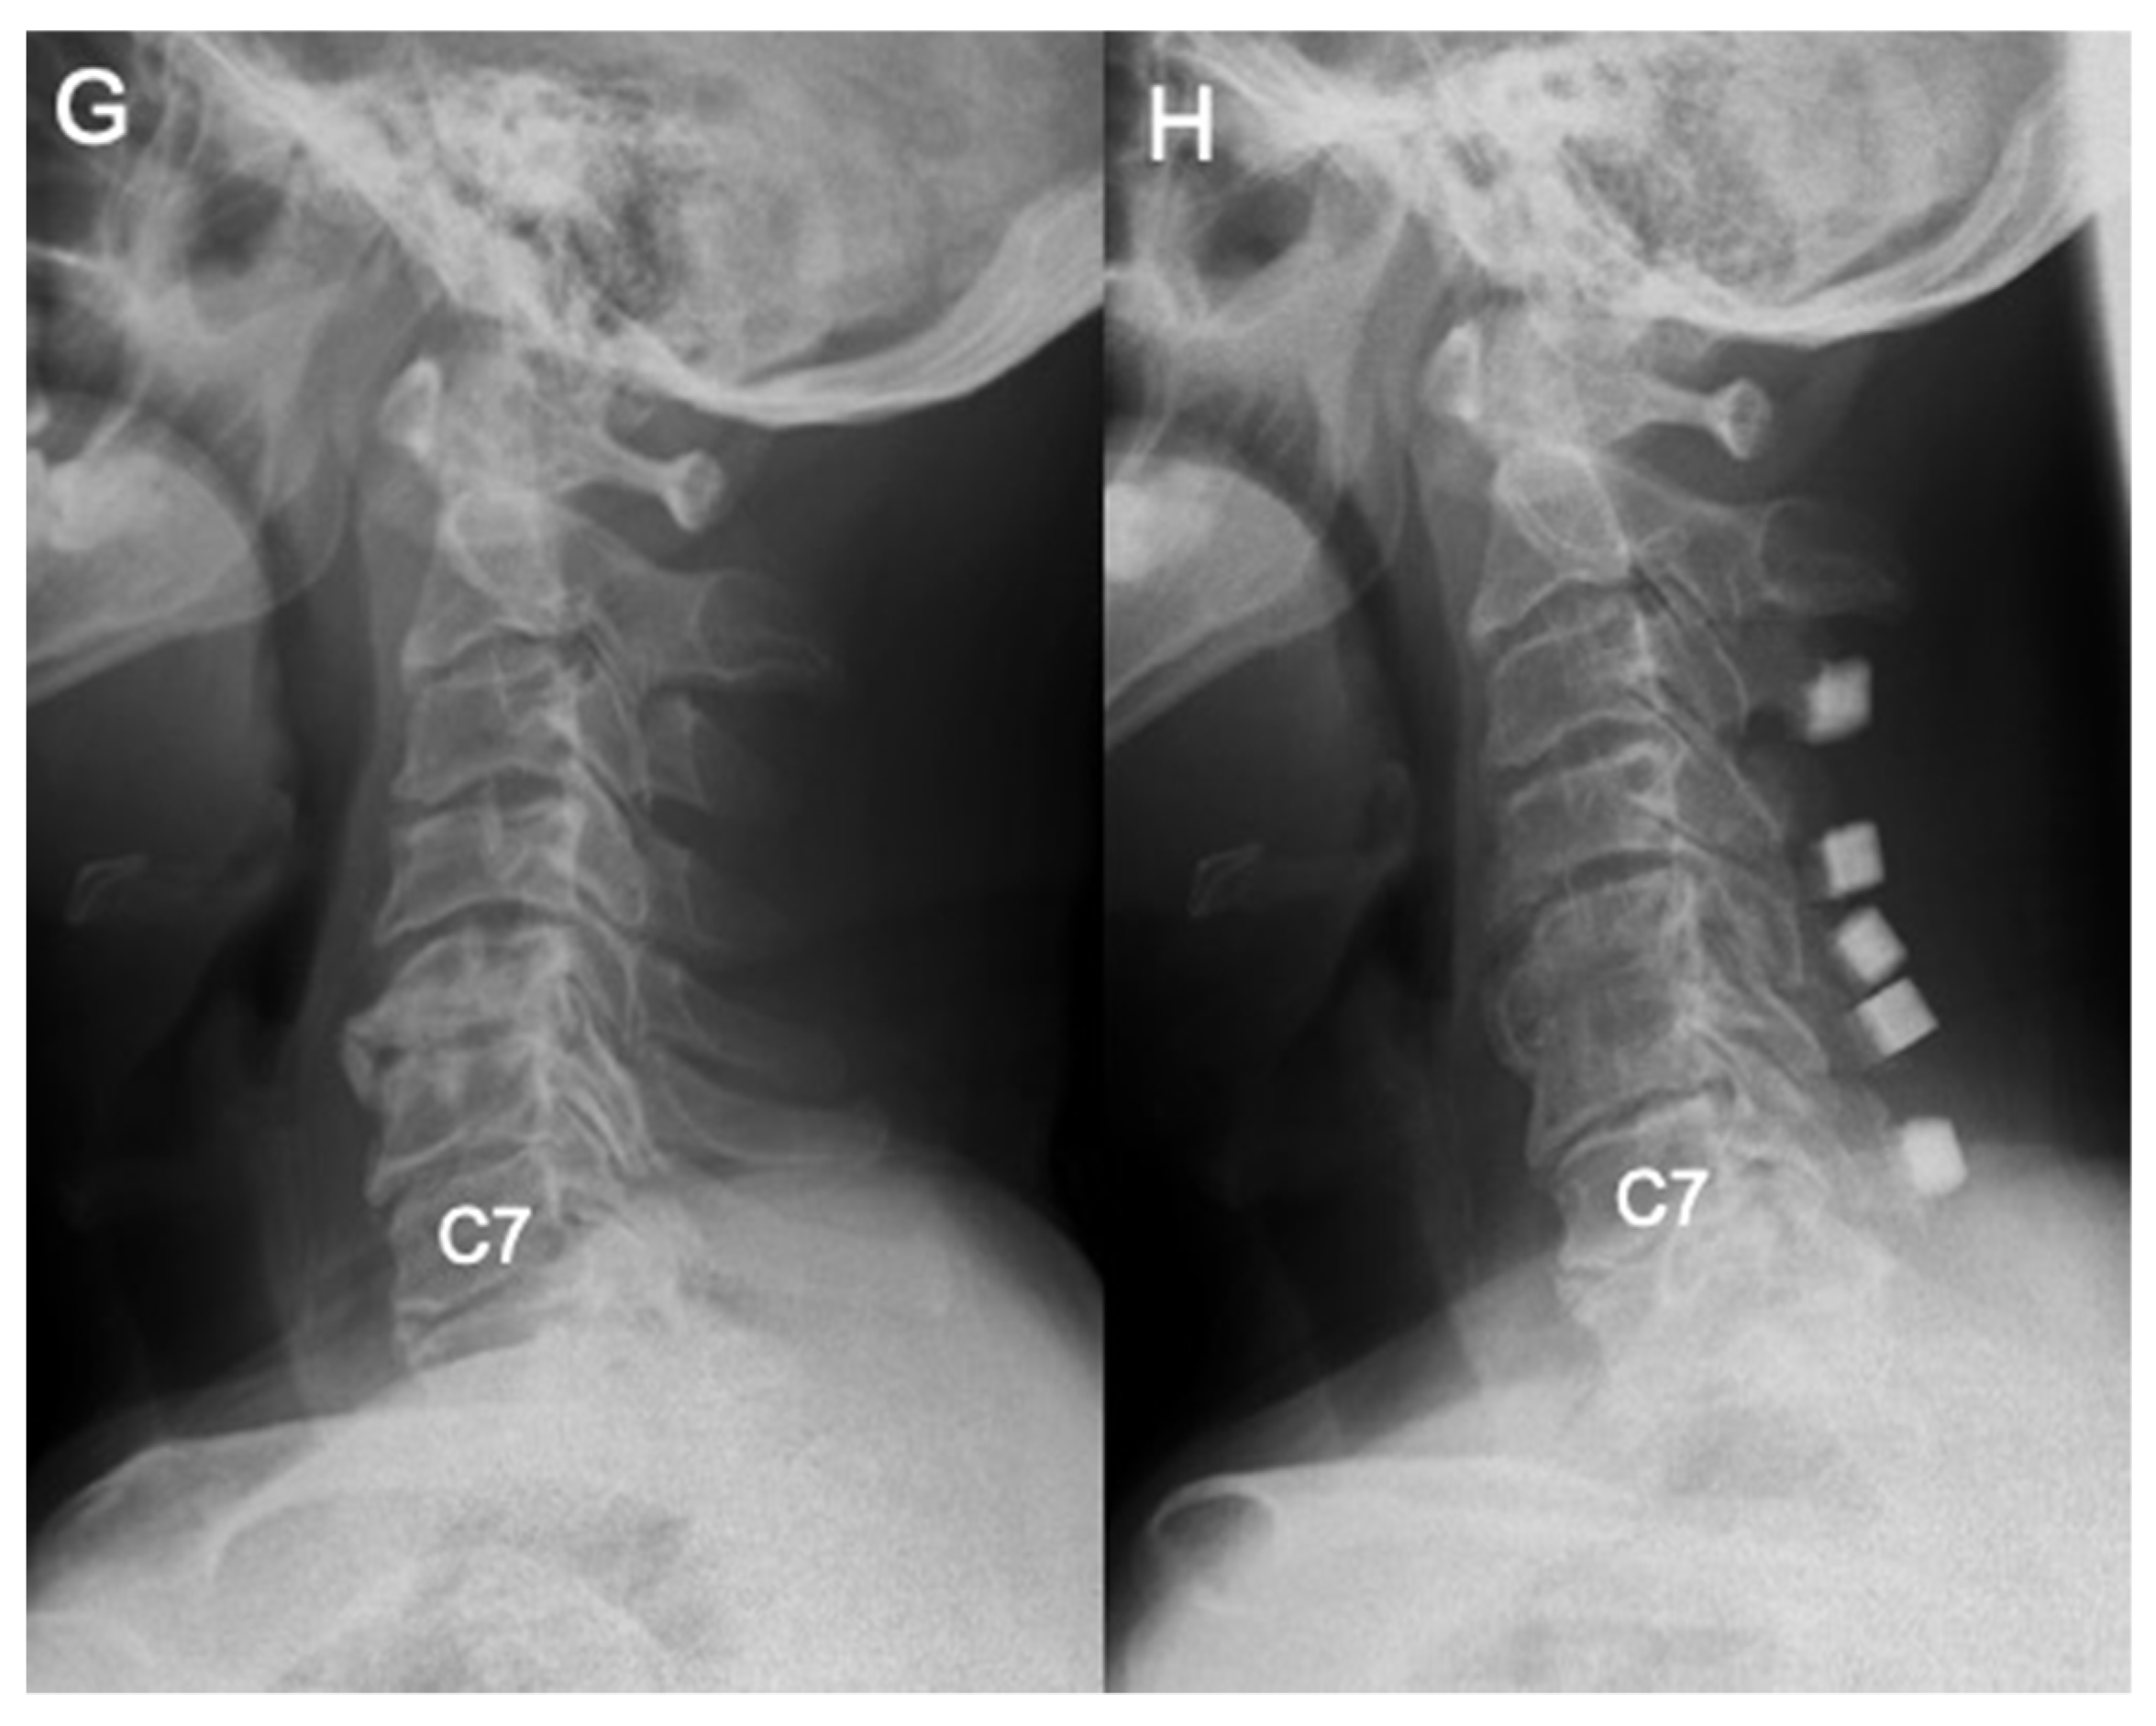

Differences in Demographic and Radiographic Characteristics between Patients with Visible and Invisible T1 Slopes on Lateral Cervical Radiographic Images

2.2. Radiological Assessment